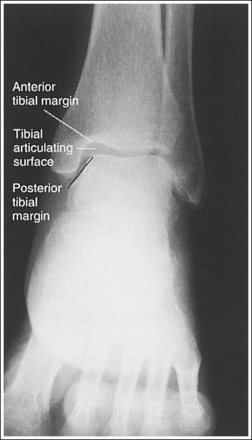

• Evaluating the openness of the tibiotalar joint. On an AP ankle projection, determine whether an open joint was obtained and whether the tibia is demonstrated without foreshortening by evaluating the anterior and posterior margins of the distal tibia. On an AP ankle projection with accurate positioning, the anterior margin is demonstrated approximately 0.125 inch (3 mm) proximally to the posterior margin (see Figure 6-48). If the proximal lower leg was elevated or the central ray was centered proximal to the tibiotalar joint, the anterior tibial margin is projected distally, resulting in a narrowed or obscured tibiotalar joint space (see Image 34). If the distal lower leg was elevated or the central ray was centered distal to the tibiotalar joint, the anterior tibial margin is projected more proximally to the posterior margin than on an AP ankle projection, expanding the tibiotalar joint space and demonstrating the tibial articulating surface (see Image 35).

• Evaluating the openness of the tibiotalar joint. On an AP oblique ankle projection, you can determine whether the positioning and central ray alignment goals have been met by evaluating the anterior and posterior margins of the distal tibia. On an AP oblique ankle projection with accurate positioning, the anterior margin should be visualized approximately 0.125 inch (3 mm) proximal to the posterior margin. If the proximal lower leg was elevated or the central ray was centered proximal to the tibiotalar joint, the anterior tibial margin is projected distally, resulting in a narrowed or obscured tibiotalar joint. If the patient's distal lower leg was elevated or the central ray was centered distal to the tibiotalar joint, the anterior tibial margin is projected too far proximal to the posterior margin, expanding the tibiotalar joint space and demonstrating the tibial articulating surface (see Images 39 and 40).

The tibiotalar joint space is expanded. The anterior tibial margin has been projected proximal to the posterior margin, and the tibial articulating surface is demonstrated. Either the distal tibia was elevated or the central ray was centered distal to the tibiotalar joint.